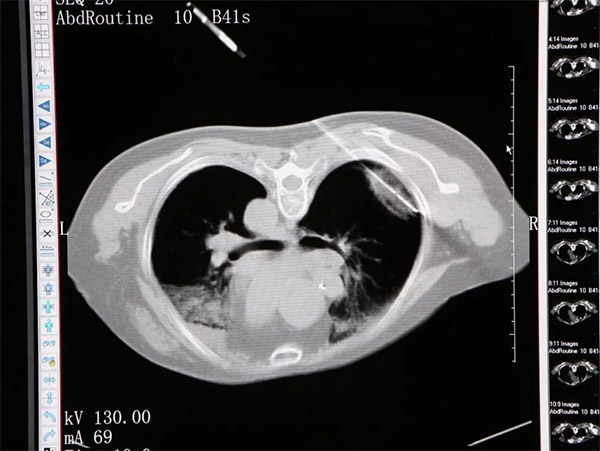

近 年来,随着我国居民保健意识的提高及早期筛查的普及,越来越多的肺内磨玻璃结节被发现。磨玻璃结节是该观察还是手术切除曾是一个让人苦恼的问题,近年来肺 微波消融术给患者带来了一个新的选择。尽管传统的外科手术仍是有效处理肺磨玻璃结节的手段,但其创伤大,费用高。而微波消融治疗作为新兴的治疗方法能造福 广大被肺磨玻璃结节困扰的患者。 一、什么是肺磨玻璃结节? 肺 磨玻璃结节指传统计算机断层扫描下发现肺内局灶性、结节状或淡薄密度增高影,样子像磨砂玻璃一样,所以叫磨玻璃结节。磨玻璃结节并不代表肺癌,事实上,其 最常见的原因还是炎性病变和增生性病变,都是良性的。磨玻璃结节发现为恶性病变的概率平均下来约为30%,因此大家大可不必发现结节就惊慌失措、谈磨色变 了。 二、哪些磨玻璃结节可能是坏东西? 配合薄层CT,动态CT观察有助于鉴别磨玻璃结节的良恶性。恶性结节通常伴有明显的分叶、空泡、胸膜凹陷征或明显的实性成分,随访过程中,如果磨玻璃结节逐渐变大、变实,或出现肿瘤微血管征象时,提示恶变可能,如果随访过程中病灶消散或者缩小,则考虑炎性成分可能性大。 三、什么是肺微波消融? 微 波消融(microwave ablation)在磨玻璃结节中应用最多,在磨玻璃结节语境中提到的消融一般都是指微波消融,也就是“微波刀”。微波消融的原理就像微波炉,一般有 915MHz或2450MHz两种频率。微波天线穿刺进靶组织,在微波电磁场的作用下,肿瘤组织内的极性分子极高速震动,分子间短时间内产生 60℃-150℃的高温。由于微波集中在一定范围内,辐射靶组织更有效率,消融时间短,温度更高、热量散失更少。微波消融在肺内还具有更高的对流性和更低 的热沉降效应,针对位置特殊的局部病灶根治效果好。 四、消融治疗有没有风险? 50%-70%的患者会出现气胸,其中需要置管引流比例在5%-20%左右,30%左右的患者会有咳血,20%—25%会出现胸腔积液,5%—10%的患者有概率出现肺内感染,大部分情况下均可对症处理解决并发症。 【专家简介】 沈阳市第六人民医院 王宁 沈阳市第六人民医院肿瘤介入科主任 主任医师 个 人简介:中共党员,潜心研究肿瘤综合治疗20余年,熟练掌握肿瘤介入治疗技巧,擅长放射性粒子植入、射频、微波消融、介入以及热化疗等肿瘤微创综合治疗。 目前已采用放射性粒子植入技术治疗肺癌、肝癌、纵隔肿瘤、胰腺癌、头颈部肿瘤、软组织肿瘤、肝门部胆管癌、淋巴结转移等恶性肿瘤3000余例,外周血管介 入治疗数百例,有丰富的微创综合治疗经验,对肿瘤放、化疗、靶向治疗、微创综合治疗有深入的研究,总结、撰写论文20余篇(第一作者及通信作者15篇), 参编专著10余部(副主编8部)。 出诊时间:每周一、三、四、五 出诊地点:2号楼1楼肿瘤介入门诊